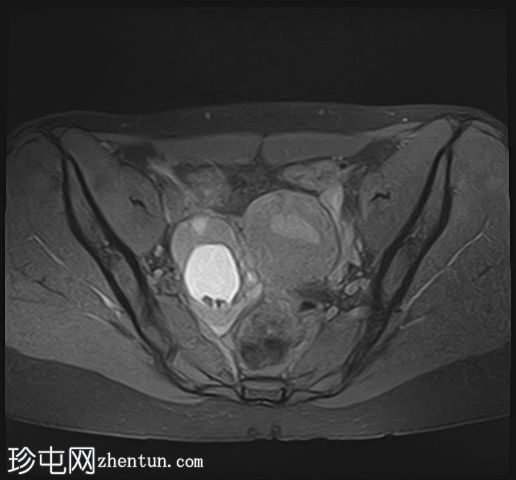

轴位T1加权像

脂肪抑制像

在右侧附件区可见一较大病灶,最大轴位和头尾径约为3 x 3.8 x 3.7 cm。该病灶在T1加权像上呈高信号,脂肪抑制像上无信号抑制,在T2加权像上呈低信号(阴影效应)。病灶壁可见T2暗点征结节,增强扫描后未见明显强化。

右侧附件区可见两个较小的类似病灶,最大径约1.2 cm。

双侧卵巢呈多囊性形态,优势卵泡保留。符合多囊卵巢(PCO)的影像学表现,T2加权像呈高信号,T1加权像呈低信号,并可见薄壁强化。

所描述的右侧附件病灶具有典型的子宫内膜异位囊肿MRI特征,包括T1高信号(无脂肪抑制)和T2低信号(阴影)。T2暗点征的存在进一步支持慢性出血性内容物。

相关的较小病灶可能代表其他子宫内膜异位种植灶。